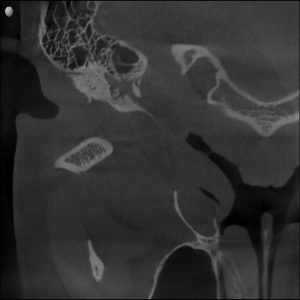

MRI confirmed bilateral disc displacement without reduction — both jaw joints had discs that had slipped out of position, causing compression and inflammation.

Clinical & Radiographic Findings

- Bilateral disc displacement without reduction

- Restricted opening (31 mm → improved to 47 mm)

- Myofascial tenderness and deep bite

- Significant parafunctional clenching pattern

Bilateral TMJ dysfunction with disc displacement and muscular hyperactivity.